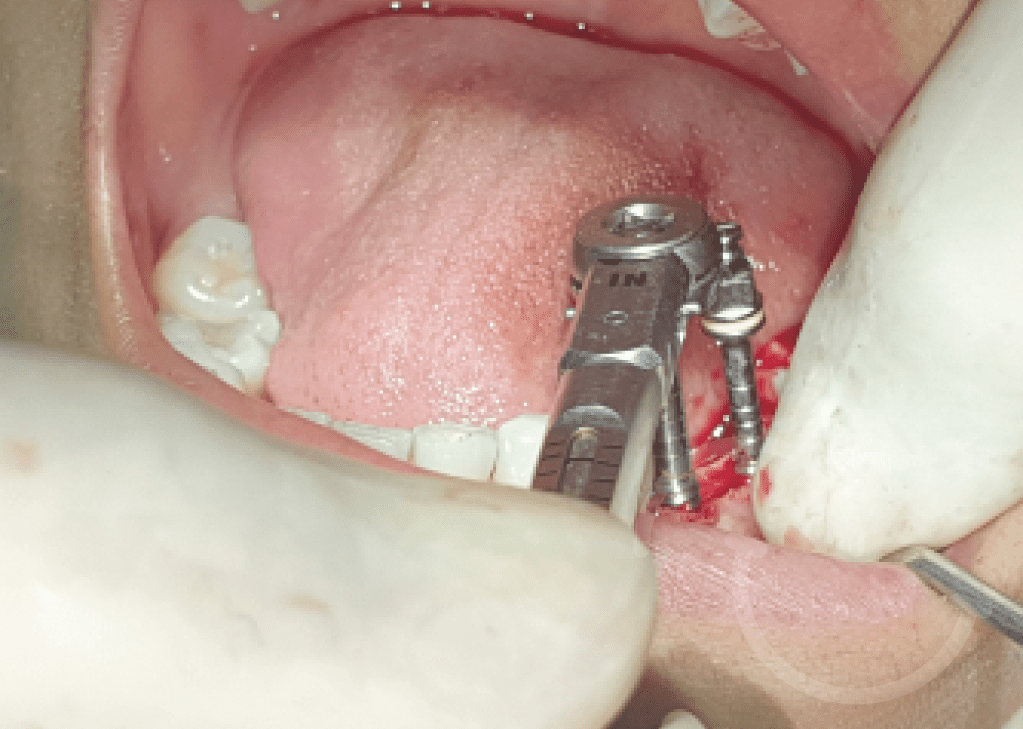

Injerto de mentón

Caso 2